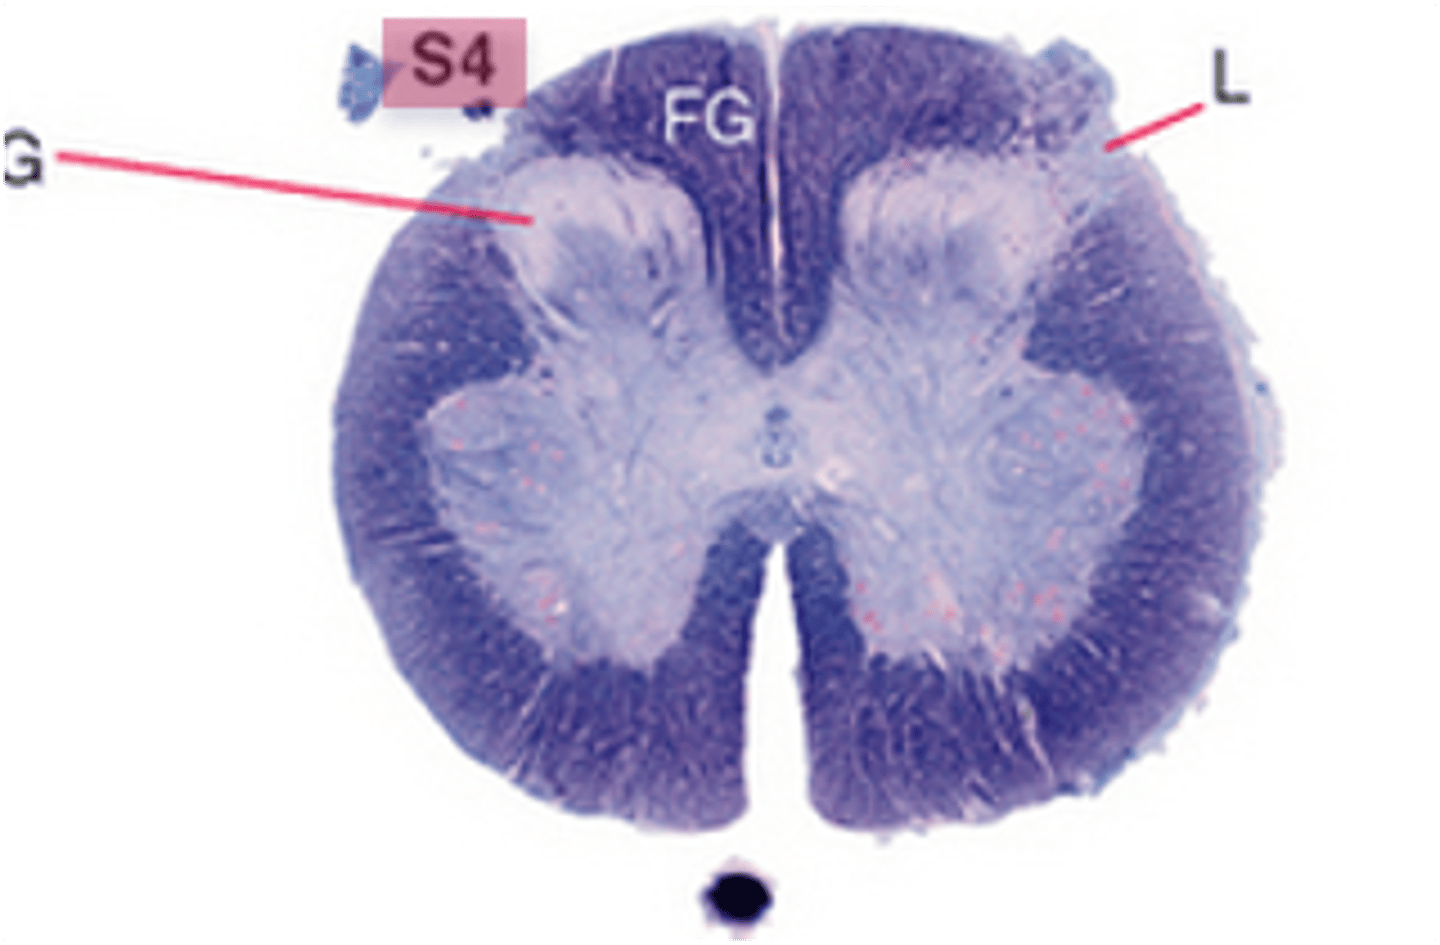

which division of the spinal cord is the most round and smaller than the lumbar division, mainly containing gray matter, but also a thin shell of white matter?

sacral

the lateral horn of the spinal cord is found on spinal levels ____-____ and ____-____

T1-L2, S2-S4